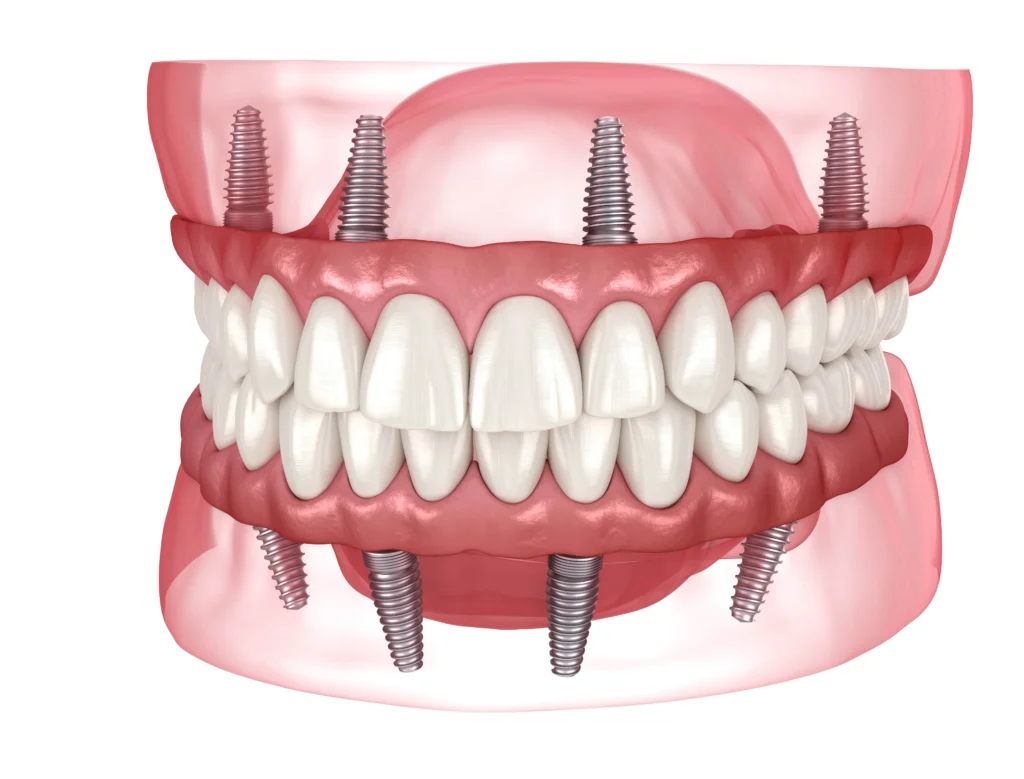

What Are All-on-4® Dental Implants? Understanding the Process

The All-on-4® procedure is a revolutionary technique designed to provide a full arch of beautiful, non-removable, replacement teeth using just four strategically placed dental implants.

Instead of needing a single implant for every missing tooth, the All-on-4 concept uses four implants placed at precise angles to maximize the use of existing jawbone structure. This often eliminates the need for complex and time-consuming bone grafting procedures.

The result is a fully fixed set of teeth that functions exactly like your natural smile. They are brushed and cleaned like natural teeth and never need to be taken out. It is the ultimate solution for patients seeking to replace traditional, removable dentures.